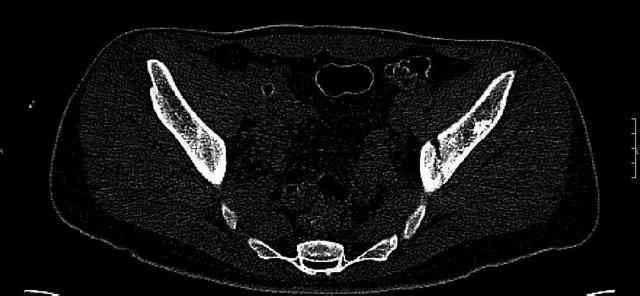

The last two images from the 3-D CT scan certainly makes the fracture look worse than the plan radiographs.

Some more images. Does it help to guess which part of the acetabulum is displaced?

Normal appearing SI joints and a healed posterior column limb... my bet's on caudal segment displacement.